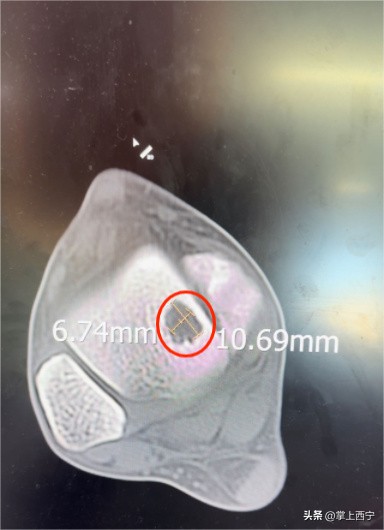

↑ 术前CT检查

经过骨二科鲍义章主任和医师团队的进一步诊察,诊断为距骨软骨损伤并收治入院。患者入院后,医护人员为患者进行了充分的术前检查,经科室医师团队进行周密的病例讨论后,完善了各项术前准备,为患者施行了自体骨软骨移植术治疗距骨软骨损伤。

出现上述情况可去正规医院创伤骨科与足踝外科门诊就诊,给予完善查体,了解足踝部的活动度是否正常,有无固定的压痛部位,除此之外,还需结合影像学检查,其中 MRI(核磁共振)检查 可以更准确地显示出关节软骨损伤的面积大小以及受伤深度等情况,为进一步治疗提供依据。